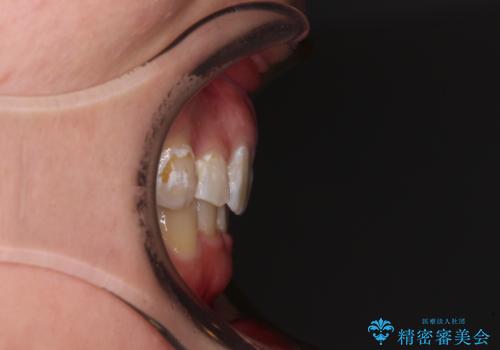

著しい八重歯を短期間で改善 ワイヤー装置による抜歯矯正

- 八重歯と下顎小臼歯の欠損を気にして来院された患者様です。

下顎小臼歯の欠損により過蓋咬合となっていたため、下顎は臼歯を起こすことで咬み合わせを改善し、八重歯は第一小臼歯2本を抜歯し、補助装置を使用して速やかに改善することとしました。

八重歯は3,4か月で速やかに改善されました。